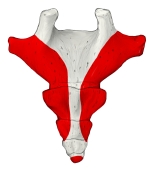

尾 骨 ( びこつ、英:coccyx )

尾骨とは 「日本人体解剖学 (上巻) 「 胎児期には9個の尾椎の原基が存在するが、胎児の成長と共に下方のものから次第に退化し、結局上方の3~5個の尾椎だけが残り融合してできた骨で、尾椎の数には個人差がある。」 また、「Wikipedia」には以下のような解説が見られる。 「Most anatomy books incorrectly state that the coccyx is normally fused in adults. In fact it has been shown that the coccyx may consist of up to five separate bony segments(区分), the most common configuration(形状) being two or three segments.」

・全体としては逆三角形の形を呈する。

・第1尾椎にあたる部分の下から第1尾椎神経が出るが、それ以下からは神経は出ない。 ・仙骨と骨化(ossification)しない場合は、椎間円板を介して関節する。(仙尾関節)